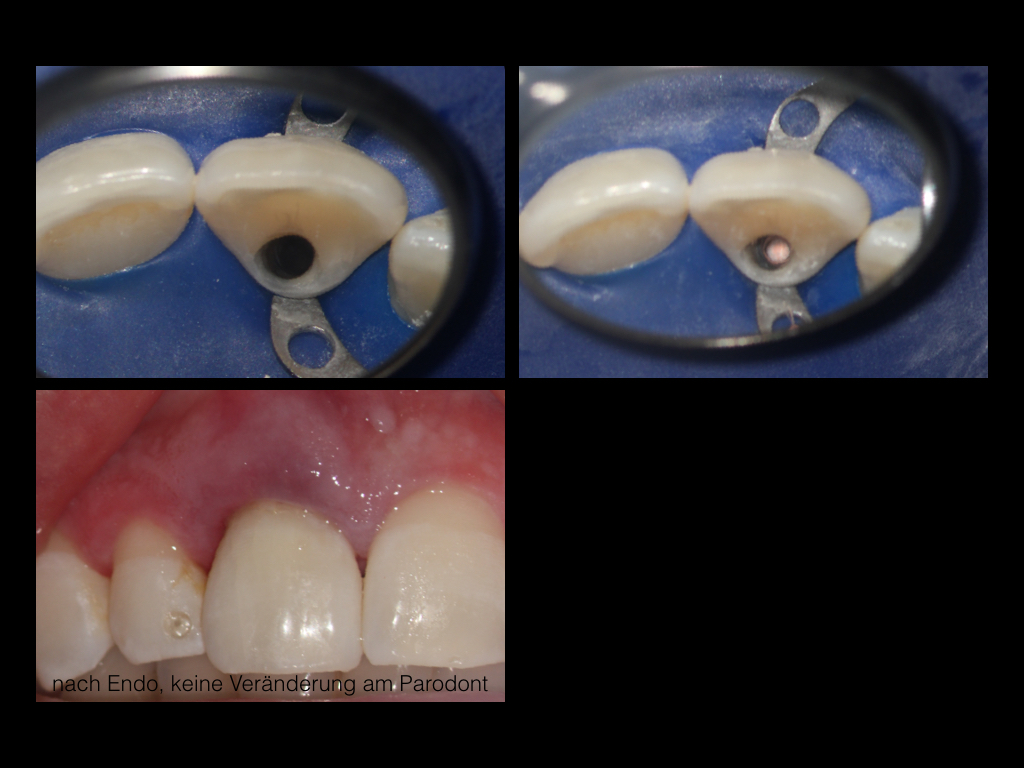

Herodontics (1)